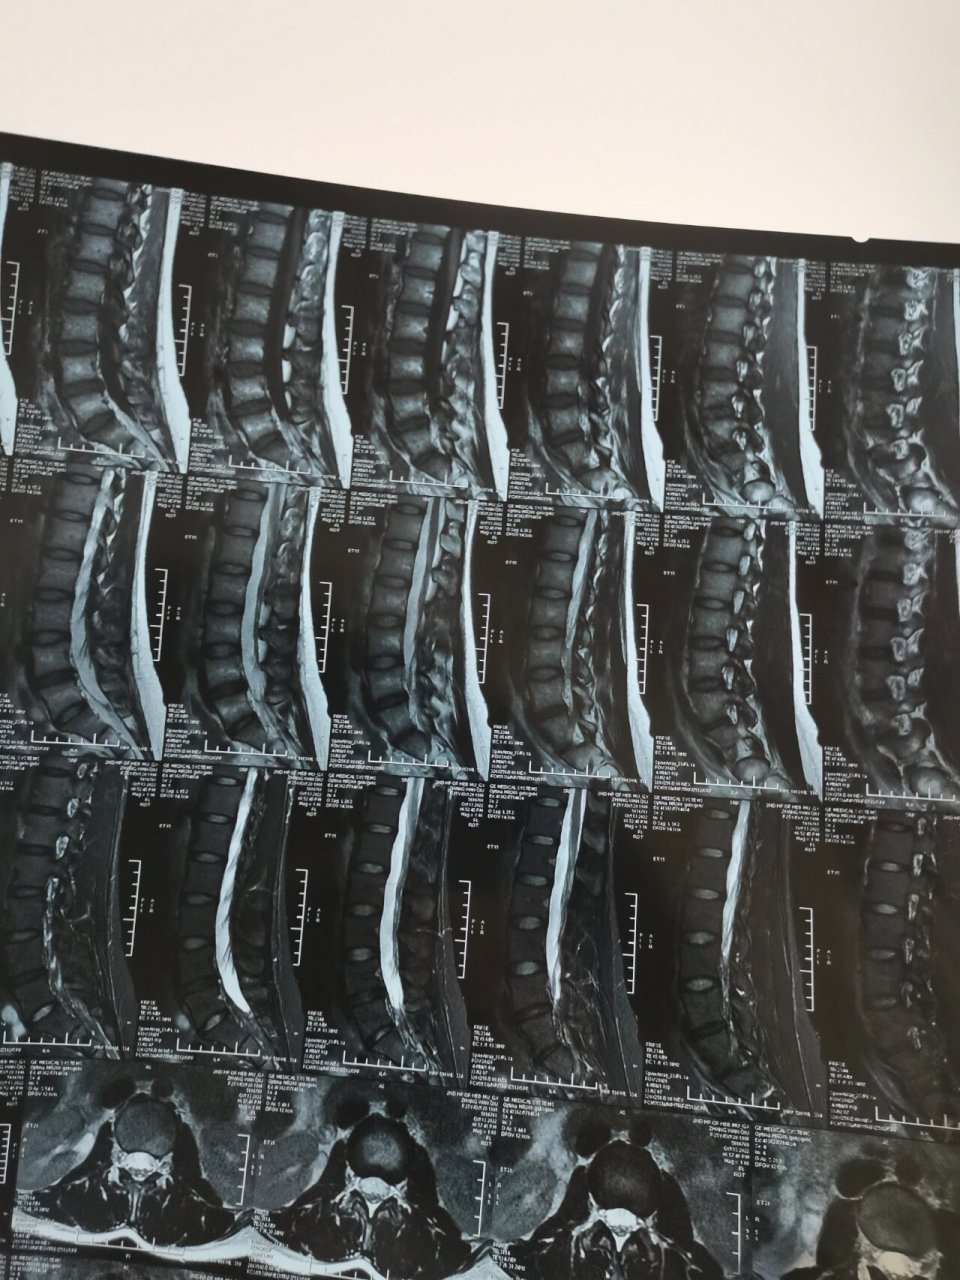

腰间盘突出的核磁片子,万能的宝子们有专业人士帮忙看看,最好附 - 抖

图片尺寸1440x1920